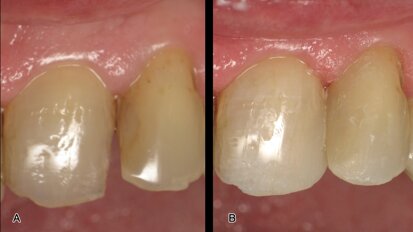

Demostración del poder del láser en un diente humano en el Greater New York Dental Meeting. (Foto: José Antonio Rosario)